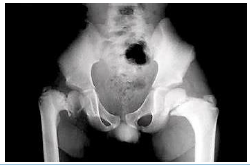

“Criança de dois anos e meio, com queixa de claudicação, apresenta a seguinte imagem. Ao exame constata-se proeminência na região trocantéria maior esquerda.”

De acordo com os dados e a imagem apresentados, trata-se provavelmente de